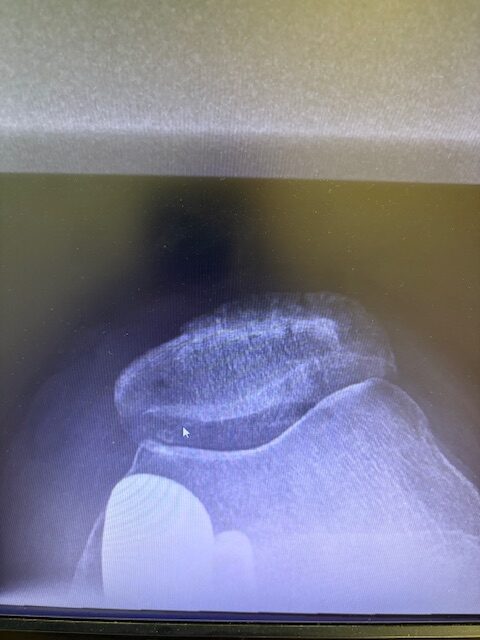

Η επέμβαση πραγματοποιήθηκε με ελάχιστα επεμβατική προσπέλαση και τοποθέτηση πρόθεσης μόνο στον έσω μηροκνημιαίο διαμέρισμα του γόνατος.

Η ακριβής προσαρμογή του εμφυτεύματος επιβεβαιώθηκε διεγχειρητικά, εξασφαλίζοντας σταθερότητα και φυσική κίνηση της άρθρωσης.

Στον ασθενή τα εμφυτεύματα που χρησιμοποιήθηκαν είναι της εταιρείας Zimmer-Biomet Persona Μηριαίο μέγεθος 6, κνημιαίο μέγεθος Η και ενθέμα (inlay) Η li. 8mm.